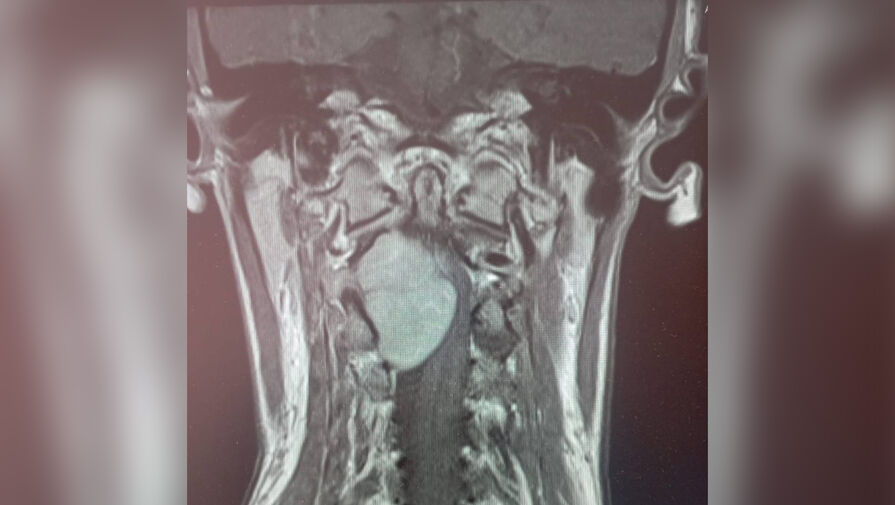

Врачи больницы скорой помощи Липецка прооперировали 35-летнюю женщину с огромной опухолью в шейном отделе позвоночника. Об этом региональный министр здравоохранения Анна Маркова сообщила в своем Telegram-канале.

Пациентка обратилась к медикам с жалобами на отнимающиеся руки и ноги. МРТ показало, что проблема кроется в шейном отделе позвоночника, где выросло большое новообразование.

«Шейный отдел — очень опасная локализация. Спинной мозг здесь переходит в головной, кроме того, в шее проходит большая нервно-сосудистая магистраль. Опухоль в этом отделе представляет серьезную угрозу и может привести к парализации», — рассказал нейрохирург больницы Леонид Осолодченко.